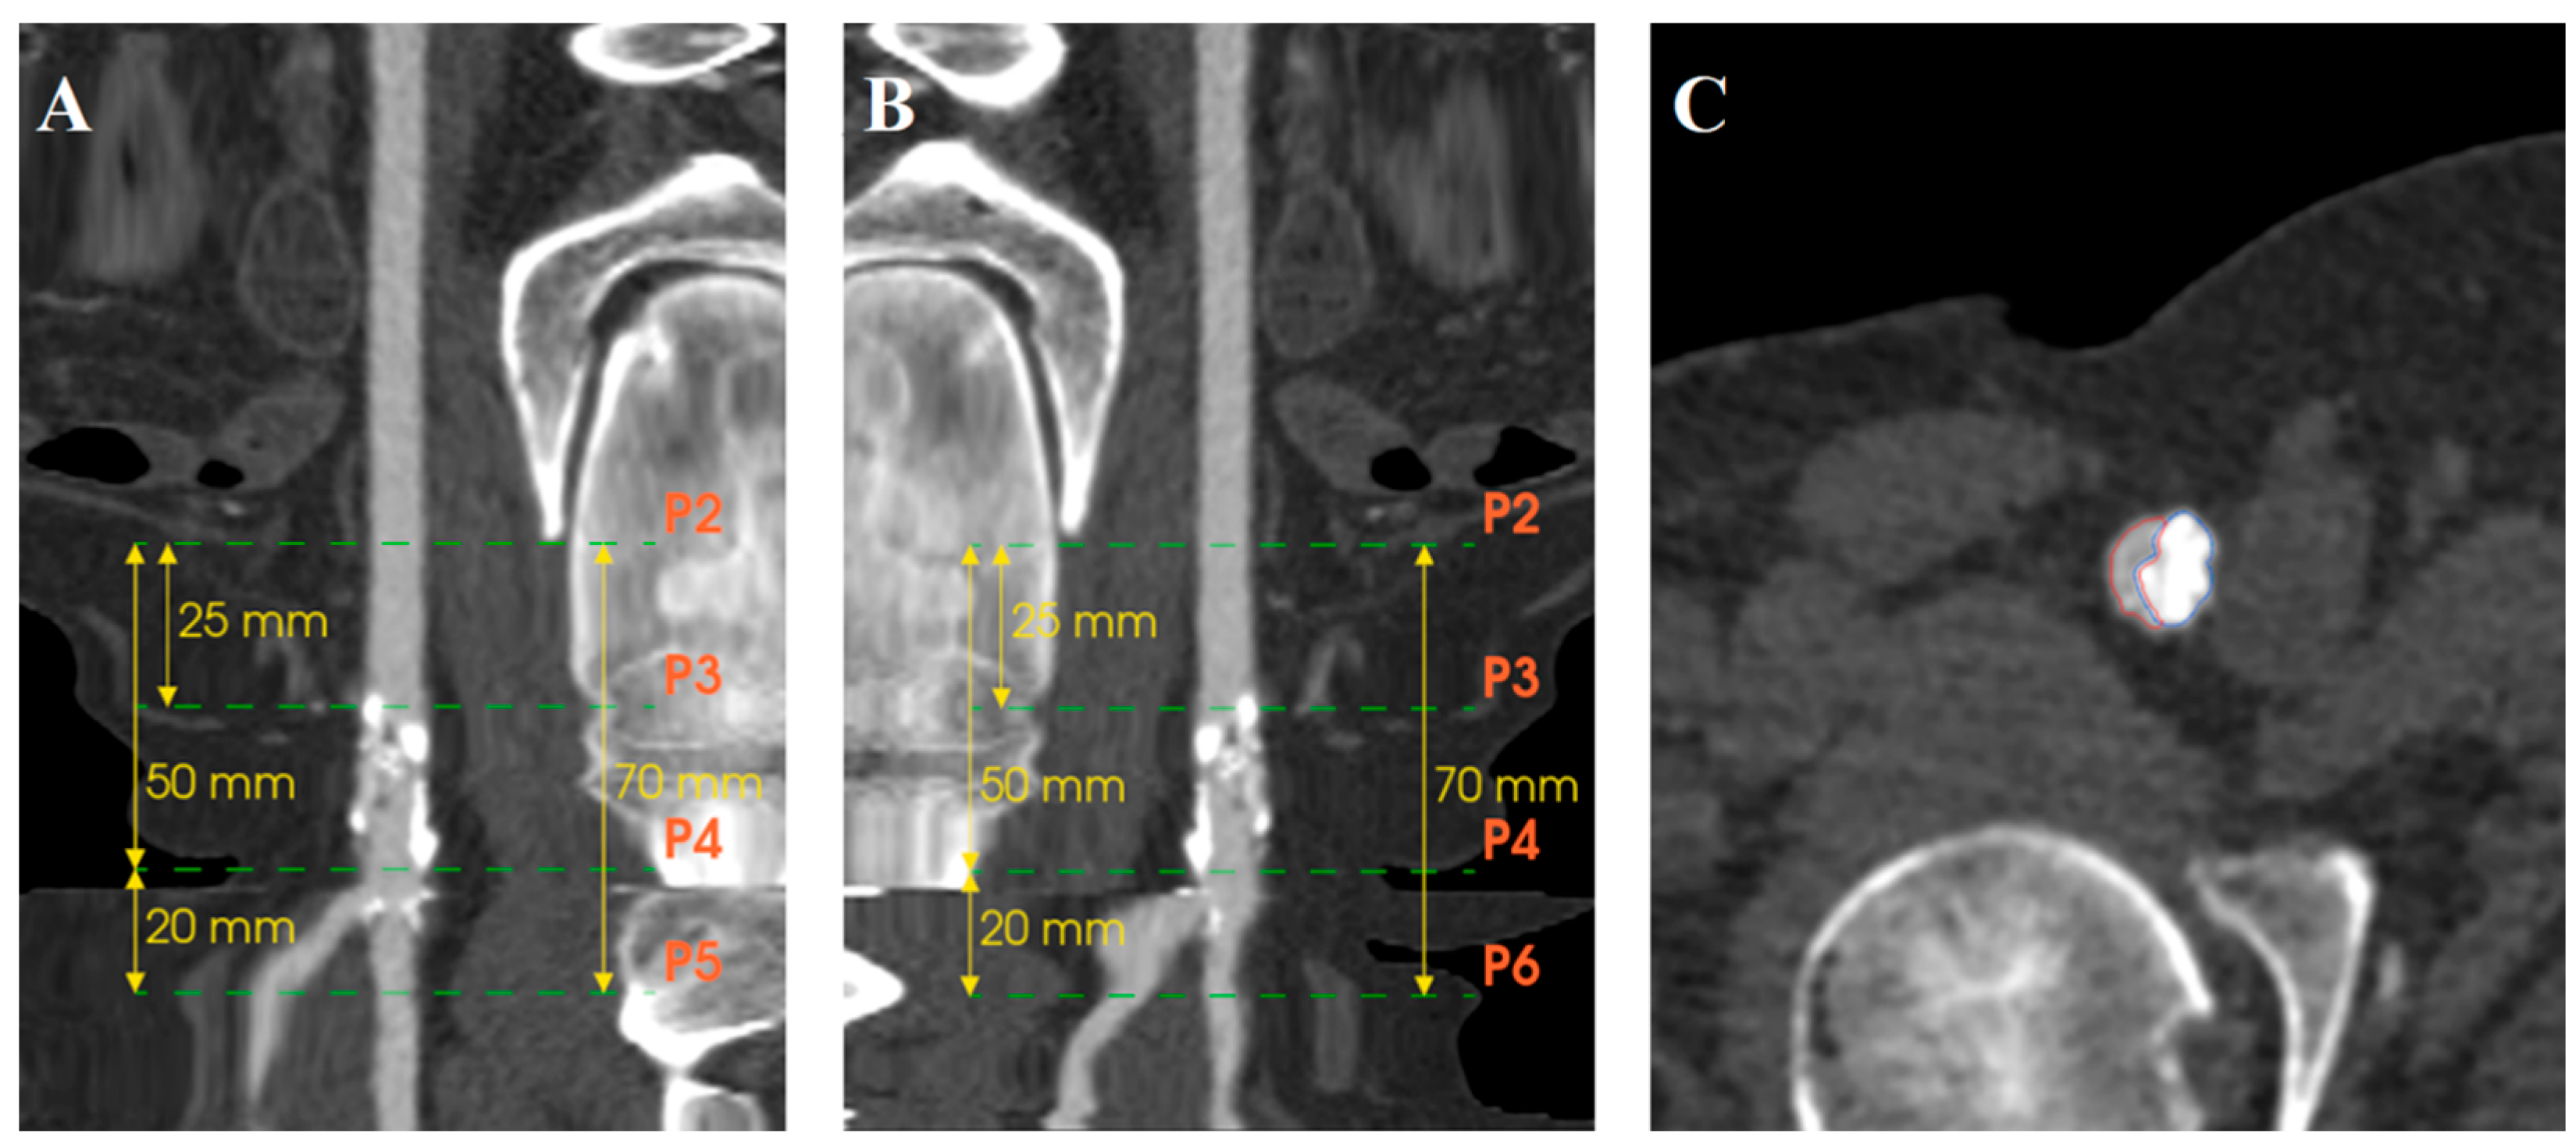

3.3. Quantification of Calcifications